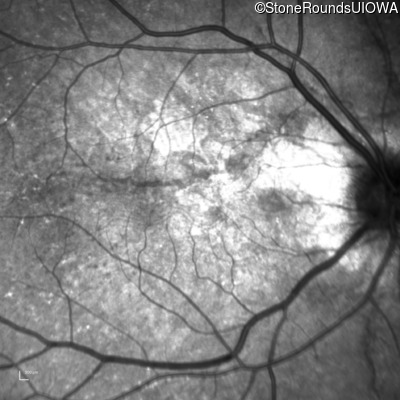

Infrared Fundus Photograph - Left - 20/20 -2

Exemplar